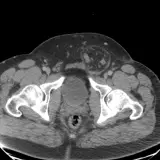

Over 2,100 interactive radiology cases, curated by radiologists for your level of training. Scroll, window, and view cases full screen — just like on PACS. Click linked findings in each writeup to jump straight to them on the image. Cases include sample reports, a focused discussion section, original illustrations, and videos.

PACSで期待されるツールを完備した完全インタラクティブな症例 — スクロール、ウィンドウ調整、ズーム、パン、計測、ROI、フルスクリーンモード。

重要な所見を症例画像上に直接ハイライトする豊富なアノテーション。症例解説内のリンクされた所見をクリックすると、スキャン上の正確な位置へジャンプできます。